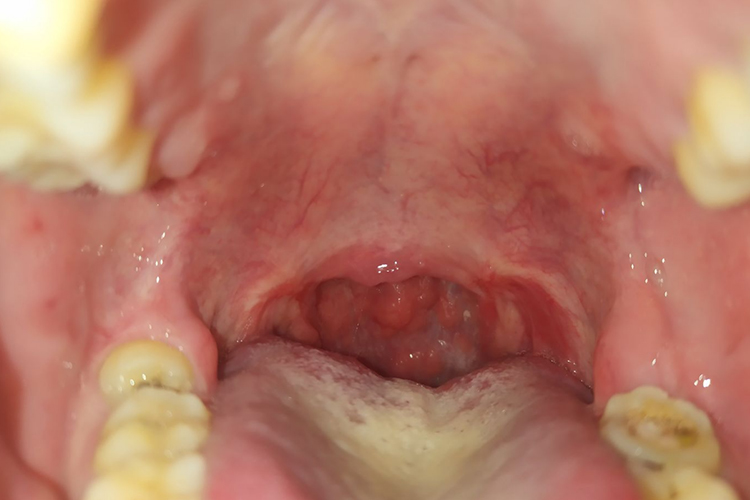

扁桃体摘除术后6小时伤口即有白膜形成,术后第二天扁桃体窝已完全覆盖白膜,术后10天内逐渐脱落。大概半个月可以完全脱落,伤口逐渐恢复。